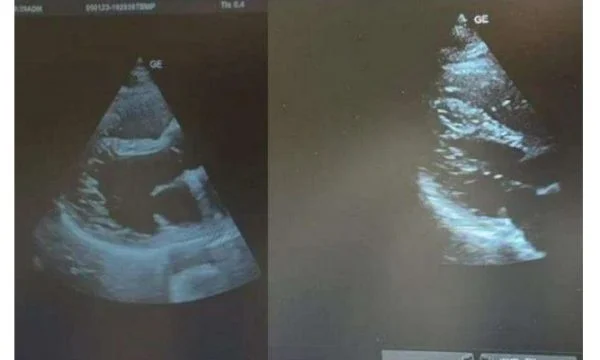

Sipas doktorit, pacienti, i cili është i moshës 28-vjeçare, është konstatuar me Destrocardia dhe Inversione të organeve të barkut nga e majta.

Ky është ndër rastet e rralla në botë, ndërkohë që për të riun kanë nisur shqetësimet e para shëndetësore. Sipas doktorit të mirënjohur, në të gjithë botën mund të jenë vetëm 5 raste njerëzish që kanë këtë lloj anomalie trupore.